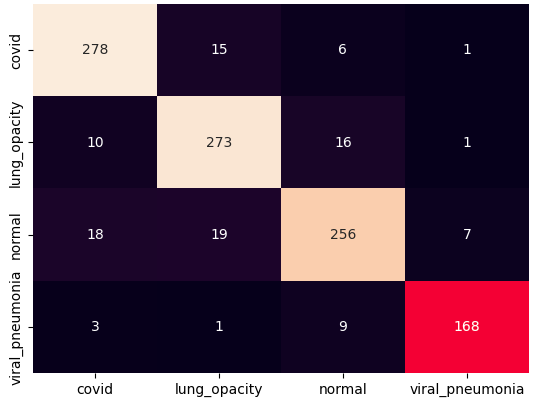

III.2 Classification results

The training procedure in all scenarios has converged. Looking at the evolution of training and validation accuracy (Fig. 11a) indicates that a larger validation dataset would be beneficial. To stabilise the classifier training a procedure of multiple training runs to select the best model is used (Materials and methods). Resulting classifiers are able to discriminate between classes with good precision, for example, see the confusion matrix of the best overall model presented in Fig. 11b. It can also be seen that for the normal class, the rate of misclassified images as COVID-19 ones is higher than for other classes. This effect is present for all models although smaller for the ones based on the EfficientNet-B0 architecture. In addition, the EfficientNet-B0 variants excel if the correct classification of viral pneumonia class images with the smallest rate of errors. However, the EfficientNet-B0 GAN augmentation scenario shows increased misclassification of healthy images which leads to a poor performance. The evolution of the training accuracy as well as confusion matrices for all models are summarised at the end of this section.

Training results for the two architectures are summarised in Figs. 13, 14, 15, 16, and Table 3. For each architecture four scenarios are considered as described in Training process part of the Materials and methods Section.